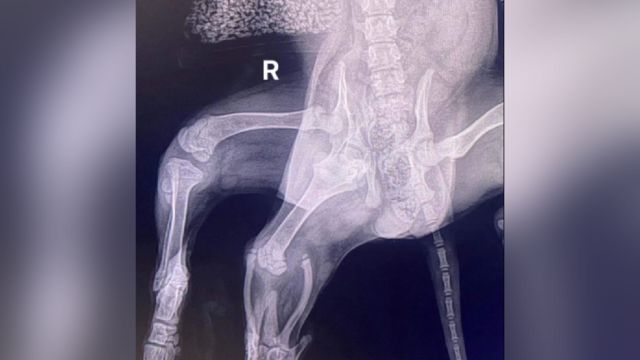

Uma radigrafia revelou que Ariel tinha duas articulações do quadril no lado direito

“Como ela tinha duas articulações do quadril de um lado, a pélvis de Ariel nunca se formou adequadamente.”

“Como resultado, sua perna direita traseira normal praticamente não tinha tônus muscular, então havia a possibilidade de que ela também pudesse ter sido perdida”.